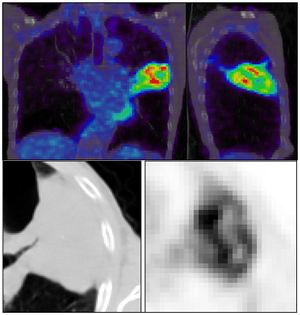

Development of a Nomogram Combining Clinical Staging with 18F-FDG PET/CT Image Features in Non-small-cell Lung Cancer Stage I-III

Publication: Eur J Nucl Med Mol Imaging. 2016 Jul;43(8):1477-85. PMID: 26896298 | PDF Authors: Desseroit MC, Visvikis D, Tixier F, Majdoub M, Perdrisot R, Guillevin R, Cheze Le Rest, Hatt M. Institution: Nuclear Medicine, University Hospital, Poitiers, France. Background/Purpose: Our goal was to develop a nomogram by exploiting intratumor heterogeneity on CT and PET images from routine 18F-FDG PET/CT acquisitions to identify patients with the poorest prognosis. Methods: This retrospective study included 116 patients with NSCLC stage I, II or III and with staging 18F-FDG PET/CT imaging. Primary tumor volumes were delineated using the FLAB algorithm and 3D Slicer on PET and CT images, respectively. PET and CT heterogeneities were quantified using texture analysis. The reproducibility of the CT features was assessed on a separate test-retest dataset. The stratification power of the PET/CT features was evaluated using the Kaplan-Meier method and the log-rank test. The best standard metric (functional volume) was combined with the least redundant and most prognostic PET/CT heterogeneity features to build the nomogram. Results: PET entropy and CT zone percentage had the highest complementary values with clinical stage and functional volume. The nomogram improved stratification amongst patients with stage II and III disease, allowing identification of patients with the poorest prognosis (clinical stage III, large tumor volume, high PET heterogeneity and low CT heterogeneity). Conclusion: Intratumor heterogeneity quantified using textural features on both CT and PET images from routine staging18F-FDG PET/CT acquisitions can be used to create a nomogram with higher stratification power than staging alone. |